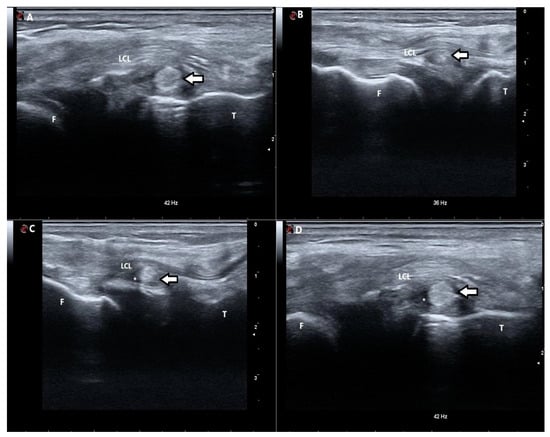

Figure 2.

Sonographic pictures of ITB strips obtained from different patients showing their normal sonographic appearance and potential pathologies. (A) Ultrasonographic short-axis scan of the iliotibial band (ITB) strip (arrow) located at the level of the tibia. The ITB strip is hyperechoic. (B) Ultrasonographic short-axis scan of the iliotibial band (ITB) strip (arrow) located between the femur and the tibia. The echogenicity of the ITB strip is slightly altered with centres of significantly decreased echogenicity. (C) Ultrasonographic short-axis scan of the iliotibial band (ITB) strip (arrow) located between the femur and the tibia. The ITB strip is hyperechoic with the surrounding hypoechogenic area, suggesting the presence of fluid (*). (D) Ultrasonographic short-axis scan of the iliotibial band (ITB) strip (arrow) located at the level of the tibia. The ITB strip is hyperechoic with the surrounding hypoechogenic area, suggesting the presence of fluid (*). F—femur; T—tibia; LCL—lateral collateral ligament; *—presence of fluid.